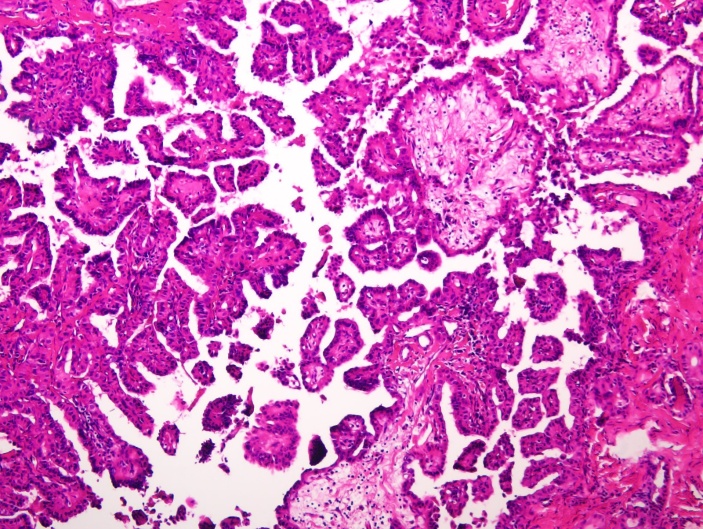

肿瘤细胞呈乳头状、微乳头状排列(图1),部分失去黏附性,极性紊乱,胞浆嗜酸性,细胞核位于顶部或偏心,突向表面呈鞋钉样排列(图2),偶见核分裂象。例1背景为桥本氏甲状腺炎,左侧为HVPTC,右侧为经典型PTC;例3可见高细胞移行区域。1例间质纤维化、钙化(图3),3例均见包膜侵犯。例1中央区淋巴结可见癌转移(7/14),淋巴结转移病灶6枚为经典型形态,1枚转移形态为鞋钉样亚型;例2中央区淋巴结3枚未见癌转移;例3送检淋巴结为纤维血管脂肪组织,未见确切淋巴结。

Figure 1. Nipple and micropapillary structure seen under microscope (HE staining ×100)

1. 镜下见乳头、微乳头结构(HE染色×100)

瘤体最大径约为1~5 cm,平均直径约3 cm,与本研究相近,偶有报道直径达10 cm,可见包膜,切面呈灰黄色[8]。镜下肿瘤细胞黏附性较差,失去极性,排列紊乱,呈微乳头结构,即缺乏真正的纤维血管轴心;肿瘤细胞表面覆盖着立方形或椭圆形上皮细胞,细胞核质比增大且无胶质,胞浆嗜酸明显,产生顶浆分泌样的胞浆凸起,似大汗腺形态,细胞核位于顶部或偏心,向表面突起似鞋钉样。此外,HVPTC具有严格的诊断标准,如超过30%的肿瘤细胞呈鞋钉样形态,常伴复杂的乳头/微乳头结构,细胞核异型性较PTC更明显[9]。当HVPTC出现肿瘤性坏死,核分裂象 ≥ 5个/2 mm2,应归为高级别分化型甲状腺癌这一大类中。